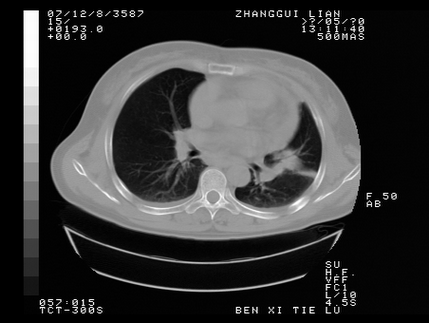

标题: CT10818:男,73,TB病史,现病史肺炎及直肠CANCER术后 [打印本页]

标题: CT10818:男,73,TB病史,现病史肺炎及直肠CANCER术后

这个请版主删除掉,这个病例我发过的,发重了,此人病史是,f,46y,胸疼,无其他原因就诊

左侧中央型肺癌伴阻塞性肺炎\\不张,左侧前上纵隔亦增宽,建议上传纵隔窗除外淋巴结转移.

考虑:左侧中央型肺癌伴阻塞性肺炎,纵隔淋巴结转移。

1)考虑为:左侧中央型肺癌伴阻塞性肺炎,纵隔淋巴结转移。2)双侧少量胸腔积液。3)心包积液。

左侧中央型肺癌伴阻塞性肺炎,纵隔淋巴结转移。

考虑左侧中央型肺癌伴阻塞性肺炎,纵隔淋巴结转移。